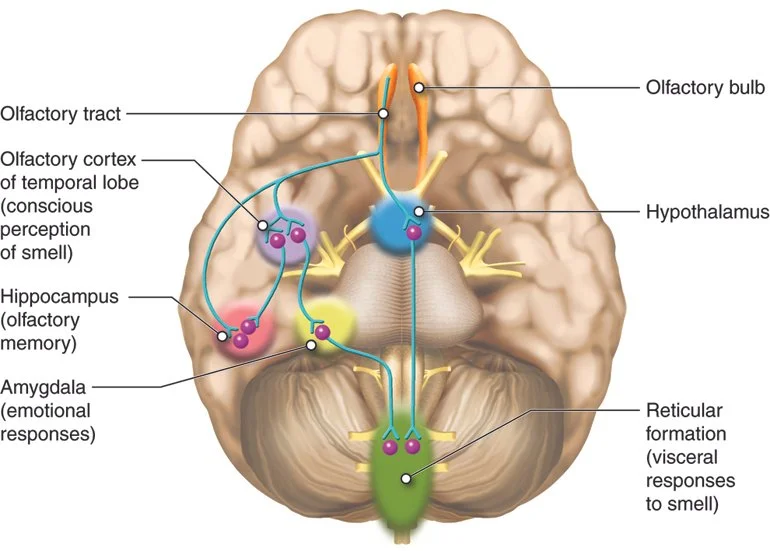

13. **Loss of Taste or Smell**The sudden loss or significant alteration of your sense of taste (ageusia) or smell (anosmia) might seem like an odd symptom to associate with lung infections, given its sensory nature. However, it can be a distinct indicator of various respiratory infections, including those that profoundly affect the lungs. This occurs when an infection triggers inflammation within the nasal passages and upper respiratory tract, disrupting the delicate sensory receptors and nerve pathways responsible for processing these chemical signals.

While most commonly and notably linked with viral illnesses such as influenza and, more recently, COVID-19, the temporary loss of these senses can also accompany other types of respiratory infections. It serves as a testament to the systemic reach of pathogens that target the respiratory system, impacting even seemingly unrelated bodily functions. The sensory disruption can be disconcerting, often highlighting a significant inflammatory process underway.

If you experience a sudden or noticeable change in your ability to taste or smell, particularly if it coincides with other cold-like symptoms, it’s a signal to consider the possibility of a respiratory infection. While often temporary, its presence should prompt you to monitor for additional symptoms and consider a medical consultation. This unique indicator can help in the broader assessment of your health and guide your healthcare provider toward an accurate diagnosis of an infection impacting your respiratory system.